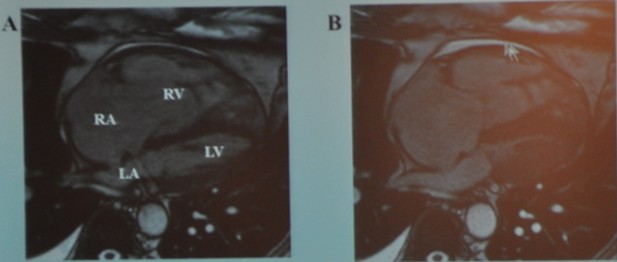

图14 MR成像

右室、右房严重扩张,伴功能低下。我们从图中可以看到左心已经被挤得很小了。

患者被诊为慢性肺源性心脏病,伴右心衰竭、肺动脉高压。当然这是一个常见病,但是做出明确诊断对患者来说也是非常重要的。